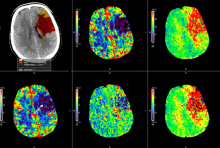

18. jūnijā Rīgas Stradiņa universitātes (RSU) Klīniskās medicīnas promocijas padomes atklātajā sēdē (Rīgā, Dzirciema ielā 16, Hipokrāta auditorijā) Arturs Balodis aizstāvēs promocijas darbu Cerebrāla infarkta agrīnas attēldiagnostikas un reperfūzijas taktikas saistība ar radioloģisko un klīnisko iznākumu.

Akūts cerebrāls infarkts jeb išēmisks insults ir viens no galvenajiem nāves un ilgstošas invaliditātes cēloņiem pasaulē. Išēmiska insulta ārstēšanā izšķirīga nozīme ir laikam no simptomu parādīšanās brīža līdz efektīvai ārstēšanai.